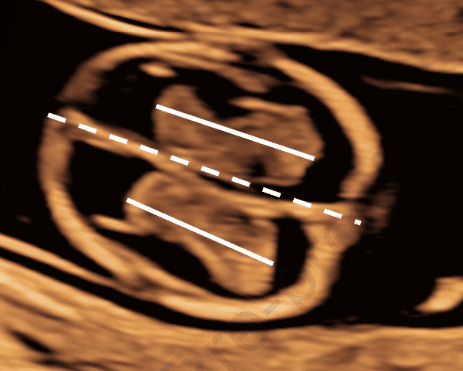

A Utilização da Relação Espessura Prenasal/Comprimento do Osso Nasal para Detecção de Trissomia 21